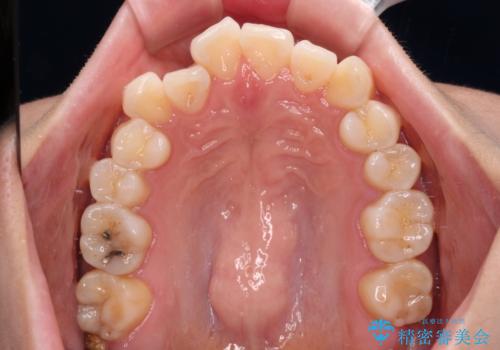

- 前歯のデコボコと、上下前歯が接触せずに前に飛び出していることを気にして来院された患者様です。

舌の突出癖が強く、それが原因で上顎歯列全体が前方に突出し、上下前歯が接触できない状態となっていました。

補助装置を用いて上顎臼歯を後方移動させ、歯列を整えながら前歯部の接触を図ることとしました。